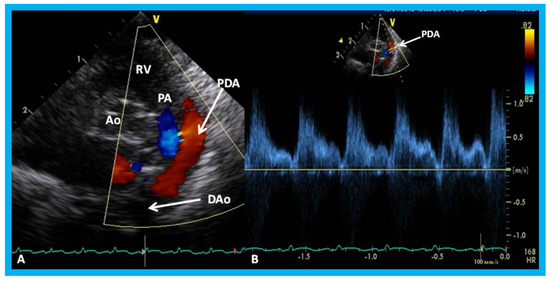

16. The Role of Echocardiographic Investigation in the Evaluation of Patent Ductus Arteriosus in the Preterm Babies

The PDA produces left-to-right shunt, largely in proportion to the minimal ductal diameter. In premature babies, such shunts produce pulmonary and cardiac compromise. Although the clinical features, chest x-ray, and serum brain natriuretic peptide (BNP) levels are helpful in identifying a PDA, hemodynamically significant PDAs are best detected and quantified with the help of echo-Doppler studies [33,34,35]. The echocardiographic finding of PDA in the premature were reviewed in detail elsewhere [33,34,35] and may be summarized as follows. The left atrium (LA), LA:aortic root (Ao) ratio (<1.4:1), and the left ventricle (LV) are expected to be normal in size in small PDAs, and the systolic function of the LV is preserved. In large PDAs, dilatation of the LA and LV and increase in LA:Ao ratio is (>1.6:1) are seen. At first, the function of the LV is normal or hyperdynamic, and with time, the function of the LV may get worse with consequent elevation in LV end-diastolic and LA pressures. These hemodynamic abnormalities may cause further worsening of the respiratory function. In babies with moderate PDAs, the parameters in are in middle with moderately dilated LA (LA:Ao ratio of 1.4 to 1.6) and LV. In the majority of the babies, the systolic function of the LV remains normal.

In small PDAs, the Minimal ductal diameter (MDD) is small and there is a high Doppler velocity across the PDA (Figure 32), while in large PDAs, the MDD is large and there is a low Doppler velocity across them (Figure 33). In moderately sized PDAs, these parameters are somewhere in between. The pulmonary artery (PA) pressures are usually normal in small PDAs, whereas the PA pressures are probably elevated in large PDAs. While the above statements are mostly accurate, the pressures in the PA also depend upon the magnitude of pulmonary parenchyma disease. Furthermore, in very low birth weight infants, the pressures in the PA may not be increased corresponding to the pulmonary parenchyma disease because of underdeveloped pulmonary vasculature in the premature.

Lastly, in small PDAs, normal diastolic anterograde flow is seen descending aorta (Figure 34), while in large PDAs, either no normal anterograde diastolic flow or retrograde diastolic flow (Figure 35) is seen in the descending aorta. Most of the medium-sized PDAs have normal diastolic anterograde flow in the descending aorta.

Clinicians caring for premature babies may be able to determine the size of the PDA by the evaluation of the diameter of the LA, LA:Ao ratio, the LV dimension, estimated pressures in the pulmonary artery, MDD, magnitude of Doppler flow velocity across the PDA, and flow patterns in the descending aorta (Table 2). A baby with medium-to-large PDA in association with respiratory compromise may be characterized as having hemodynamically significant PDA [33,34,35].